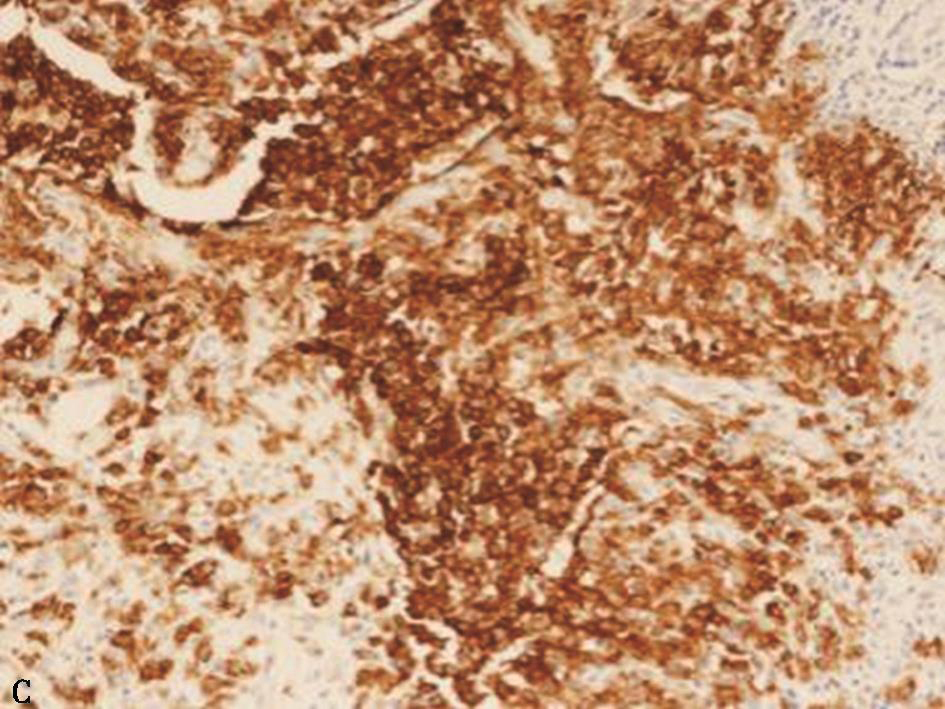

1小时条评论56岁女性,以间断咳嗽、咳痰1年,痰中带血半年入院。外院胸部CT提示双肺多发病灶伴空洞;外院病理报告慢性炎症,可见轻度核异质细胞。患者反复住院抗感染治疗无显效,复查胸部CT提示肺部病灶较前进展。未发现结核、真菌等病原学证据。如何诊治? 【病例简介】 患者...